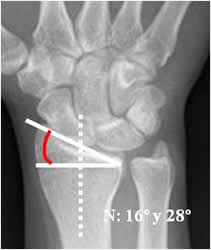

Inclinación radial:

Se traza con una línea perpendicular al eje del radio y otra línea a lo largo de su superficie distal. El valor normal es entre 16º y 28º. (12). Este ángulo disminuye en fracturas metafisisarias, impactadas, de Colles y Smith. Debe ser valorado después de la reducción e inmovilización, para dejarlo lo mas normal posible y que permita una adecuada movilidad. (1). (Fig 46).

Fig 46. Inclinación radial.

Rx AP. Angulo formado entre la perpendicular al eje del radio y una línea que pasa por la superficie articular distal, del mismo hueso.